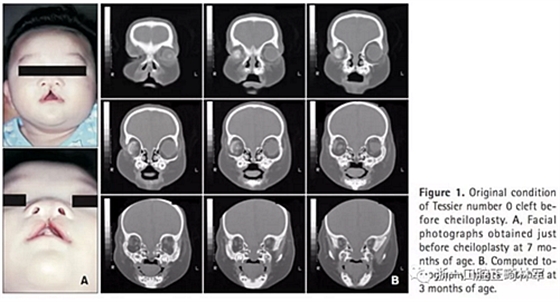

患者信息(圖1):

5歲Tessier0號面裂伴右側(cè)小眼畸形。病史如下:1月起右側(cè)佩戴義眼,7月行唇裂修復術,1歲11月時行腭成形術(V-Y),7歲7月時行髂骨移植術,8歲10月時摘除畸形眼球后植入人工植體,10歲1月時行額部懸吊及各項眼瞼整形手術。